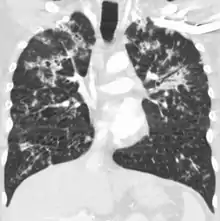

Miliary tuberculosis is a form of tuberculosis that is characterized by a wide dissemination into the human body and by the tiny size of the lesions (1–5 mm). Its name comes from a distinctive pattern seen on a chest radiograph of many tiny spots distributed throughout the lung fields with the appearance similar to millet seeds—thus the term "miliary" tuberculosis. Miliary TB may infect any number of organs, including the lungs, liver, and spleen.[2] Miliary tuberculosis is present in about 2% of all reported cases of tuberculosis and accounts for up to 20% of all extra-pulmonary tuberculosis cases.[3]

A case of miliary tuberculosis in an 82-year-old woman:

CT, 16 days after onset, showing extensive pulmonary parenchymal involvement consisting of irregular septal thickenings with ground-glass areas and centrilobular nodules with a peri-lymphatic distribution